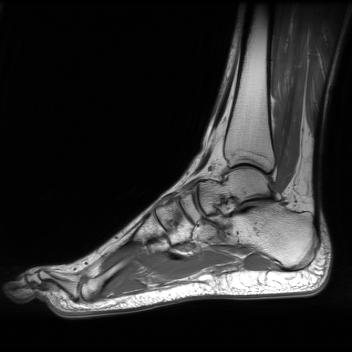

Test data: For evaluation, we used the ten 352352 MRI images in Fig. 2, which were not in the training dataset. The measurements were constructed using (1) with complex AWGN whose variance was adjusted to give a pre-masking SNR of 40 dB. For the multicoil experiments, we used coil sensitivities simulated using the Biot-Savart law, while in the single-coil case, we used .

Single-coil results: Table 1 shows that D-GEC outperformed D-VDAMP in all single-coil experiments and outperformed PnP-PDS in all but SSIM at . Figure 5 shows an example of the wavelet coefficients input to D-GEC’s denoiser at the 10th iteration, and their error relative to the true coefficients. Figure 3 shows the evolution of the standard deviation at the input to D-GEC’s denoiser in each subband; there is a good agreement between true and predicted values. Figure 6 suggests that the subband errors are Gaussian. Figure 4 shows image recoveries and error maps for one test image at .